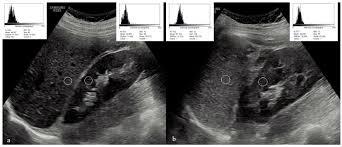

Fatores de confusão do diagnóstico ao USG? (3)

1. A avaliação qualitativa é feita de forma subjetiva;

2. O parênquima a ser comparado alterado (ex: fibrose renal);

3. Lesões focais hepáticas podem confundir.

Infiltração tumoral no lobo esquerdo simulando fígado com esteatose assimétrica.

Referências para comparação/graduação da ecogenicidade hepática ao USG? (4)

1. Parênquima renal;

2. Parênquima esplênico;

3. Vasos intra-hepáticos;

4. Diafragma.